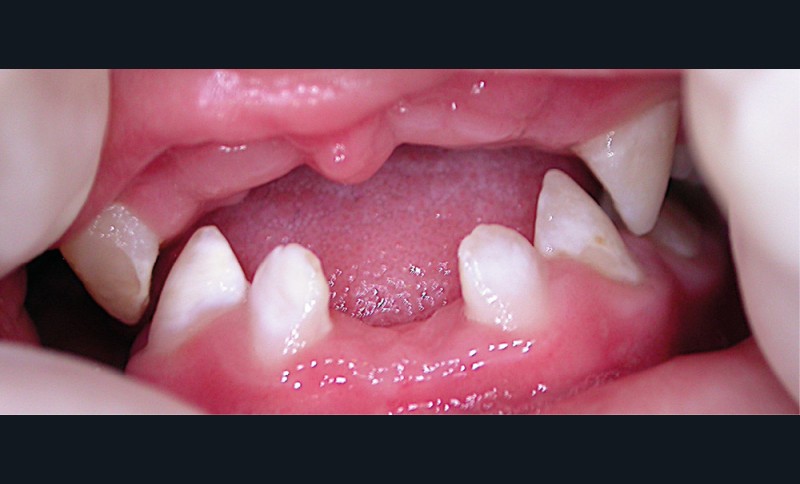

L’OMS recommande un allaitement exclusif jusqu’à l’âge de 6 mois, et associé à d’autres aliments jusqu’à 24 mois [3]. S’il n’est plus nécessaire de démontrer les bienfaits de l’allaitement sur la santé globale de l’enfant, il reste néanmoins utile d’en prévenir certaines pratiques parfois inadaptées pouvant conduire à l’apparition de carie de la petite enfance (CPE) (fig. 1 et 2). L’allaitement au sein exclusif pendant une période de 6 mois présente bien des avantages pour le nourrisson et la mère, et notamment celui de protéger contre les infections gastro-intestinales, aussi bien dans les pays en développement que dans les pays industrialisés. Par ailleurs, une mise au sein précoce, dans l’heure qui suit la naissance, réduit le taux de mortalité.

Les études soulignent également les bienfaits de l’allaitement sur la santé orale : il favorise notamment le développement de la musculature, la croissance maxillo-faciale et limite les malocclusions chez l’enfant [4]. Si la cariogénicité du lait maternel n’a pas été examinée de manière approfondie, des études suggèrent qu’elle est plus importante que celle du lait de vache, mais moins importante que celle des préparations infantiles. Ceci est à considérer notamment lors de consommations fréquentes [5, 6]. Par conséquent, il a été mis en évidence que l’allaitement maternel pourrait être un facteur de protection contre la CPE jusqu’à l’âge de 12 mois. Pour autant, des pratiques d’allaitement à la demande, après l’éruption des dents temporaires, et notamment la nuit, associées à des pratiques de cosleeping (ou co-dodo : l’enfant dort avec la mère), contribueraient à développer la CPE après 12 mois [7, 8]. Si d’autres facteurs sont également à considérer dans le développement de la CPE [9], les études soulignent que l’allaitement prolongé [au-delà de 24 mois]…